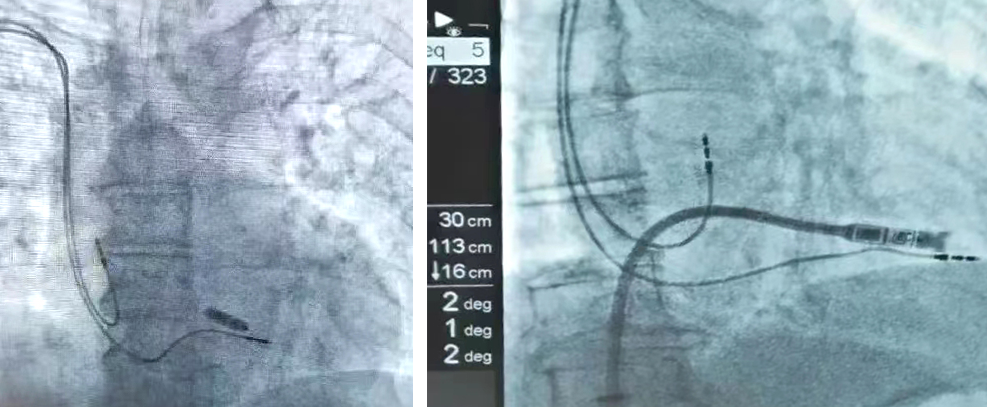

7月12日上午,『看齐』记者在齐医附属三院心血管内科二病房,见到了刚做完无导线起搏器植入手术的患者崔大爷。他激动地告诉记者,非常感谢齐医附属三院医生们利用精湛的医术,让自己重获健康。采访中记者了解到,崔大爷是一位84岁高龄的患者,房颤伴三度房室传导阻滞,七年前植入的传统起搏器电极导线磨损故障。近几年一直因房颤口服抗凝药物治疗。传统治疗方案需在对侧重新植入新的起搏器,会面临囊袋血肿、感染、多根导线引发三尖瓣关闭不全恶化心功能等风险。

经过详细分析患者情况和充分考虑患者及其家属意愿后,齐医附属三院心血管内科二病房负责人汤柏赞和刘灿君医生,为患者量身定制了缜密的手术方案,采用无导线起搏器进行植入。

齐医附属三院心血管内科二病房负责人汤柏赞告诉记者,无导线起搏植入技术,20分钟就可以结束既往一个小时的手术,术后6小时就可以下床活动,恢复的特别快,对于高龄的人群非常合适。相信这种新技术,也可以使更多的人群获益。